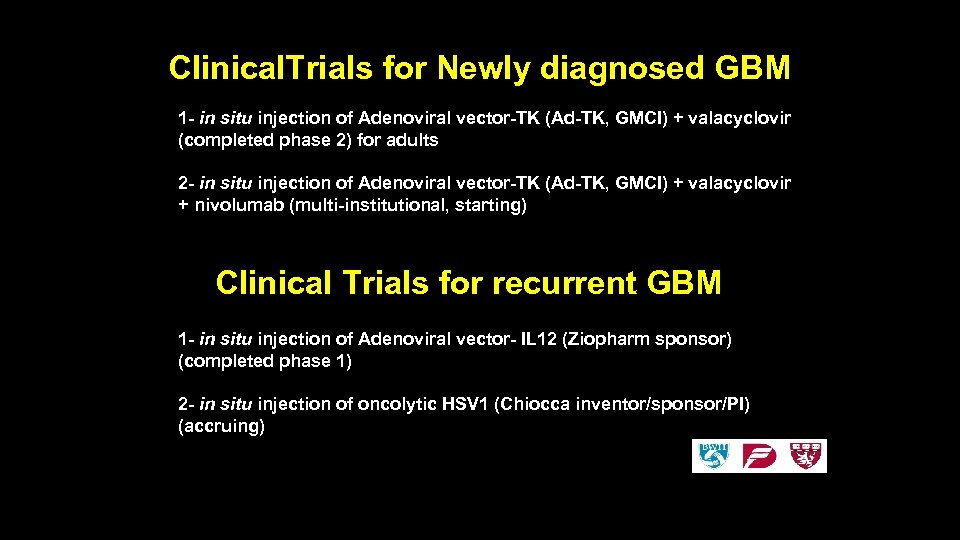

Clinical. Trials for Newly diagnosed GBM 1 - in situ injection of Adenoviral vector-TK (Ad-TK, GMCI) + valacyclovir (completed phase 2) for adults 2 - in situ injection of Adenoviral vector-TK (Ad-TK, GMCI) + valacyclovir + nivolumab (multi-institutional, starting) Clinical Trials for recurrent GBM 1 - in situ injection of Adenoviral vector- IL 12 (Ziopharm sponsor) (completed phase 1) 2 - in situ injection of oncolytic HSV 1 (Chiocca inventor/sponsor/PI) (accruing)